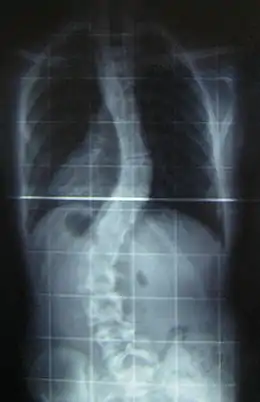

![]() Radiografía de una joven de 16 años y 8 meses con escoliosis vista de frente, de pie y con ropa (los pendientes y los aros del sostén son claramente visibles) | ||